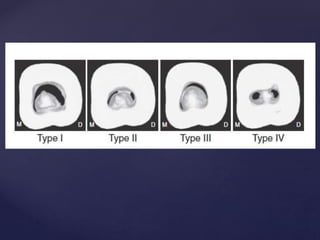

o Management of C-shaped Canals

1. Apical 2. Middle 3.Coronal 4. Combination Types according to it’s location